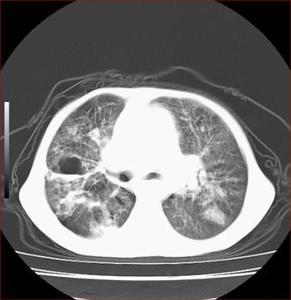

肝切面形态饱满,体积增大,肝下缘变钝,